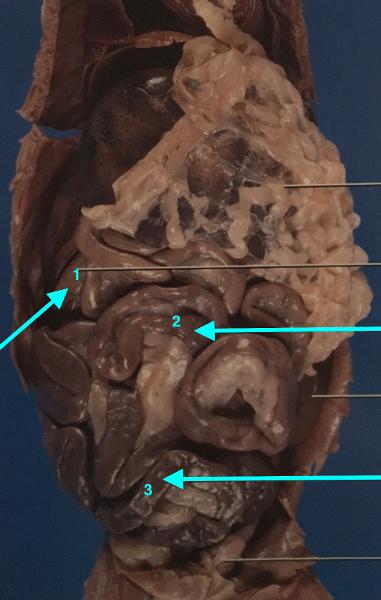

14

small intestine

- duodenum (1)

- jejunum (2)

- ileum (3)